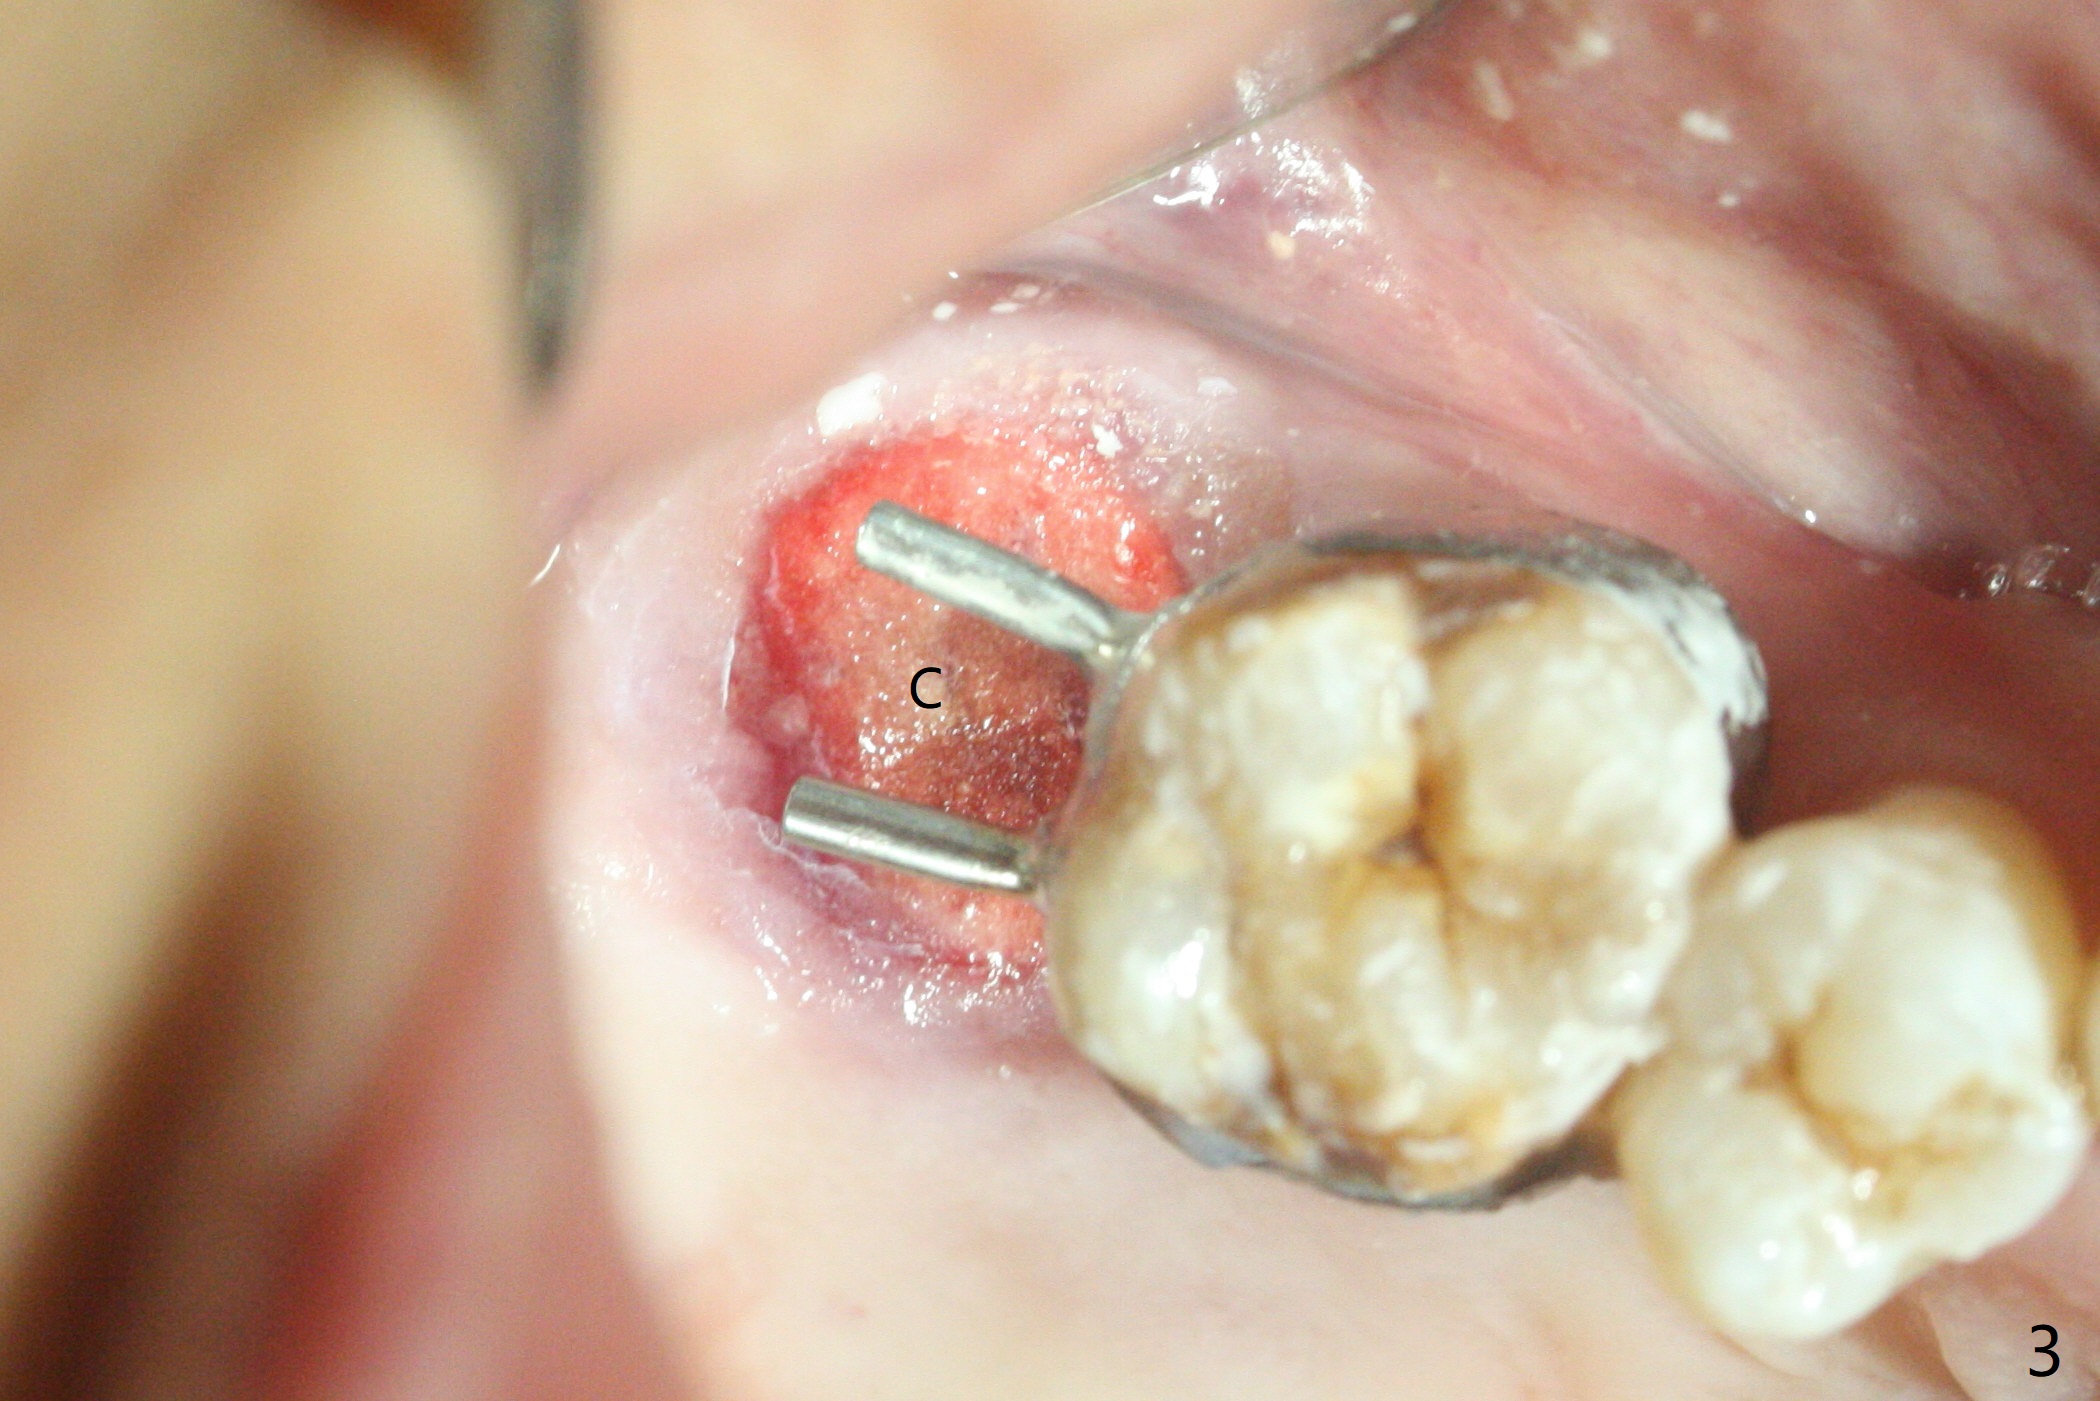

尽管右上第一,二磨牙骨质吸收严重,为了保持牙乳头,先拔除有症状第二磨牙,但是后者牙槽窝与第一磨牙之间好像没有软组织(图二:*),所以骨粉(图一,二:7)无法从前者推入后者(图二(下一个成功病例))。骨粉表面放置6个月吸收膜(GEM Cap(图三::C)),使用牙周胶水固定,而且装置牙齿空间维持器(图二:S)和牙周敷料强化固位。牙齿拔除证实腭侧牙槽窝(图四:P)上颌窦底板穿孔(^;但是没有漏气)。虽然病人已经服用Amoxicillin一周以及Z Pack(两颗,术前),为了防止感染介入上颌窦,穿孔冠部放置胶原塞(图五:黄色),然后放置骨粉(红色)。后者仿佛增加骨质高度不少(图二)。如果不够,以后再做提升。多亏间隙保持器,牙周敷料术后4天没有松动迹象(图六)。术后三周敷料颊侧有些破裂(图七),而舌侧完整(图八)。嘱咐病人正常刷牙和水牙线,让敷料自行脱落。其实术后六周敷料仍在原位,不可吸收膜粘附于敷料,两者一起去除,伤口愈合(图九),骨粉好像没有损失(图十)骨高度减少。术后4个月骨质高度继续减少(图十一)。植骨后骨质高度还与邻牙一致,密度低,可植入5x7.3毫米植体(图十二)。